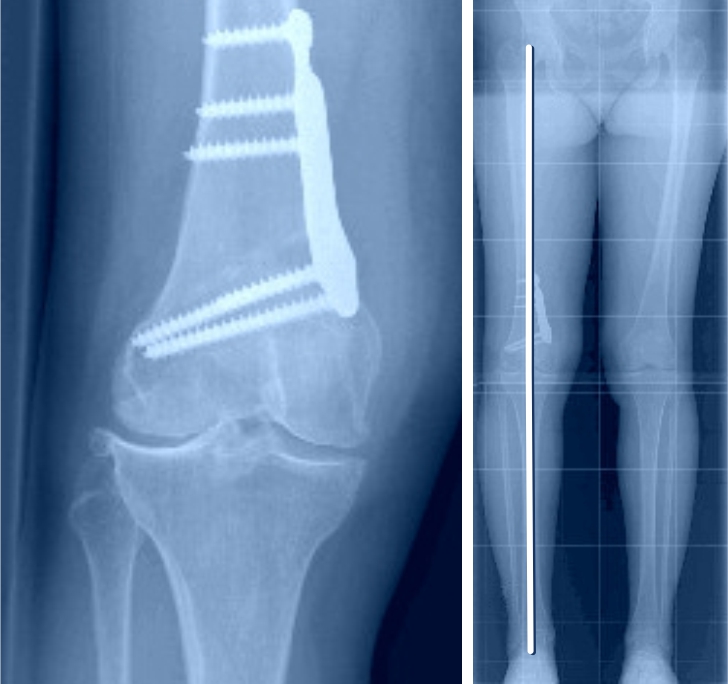

Beispiel einer sogenannten Doppel-Osteotomie, bei der sowohl am Oberschenkel als auch am Unterschenkel eine Korrektur gemacht wurde, zur korrekten Ausrichtung der Beinachse und Gelenkslinie.